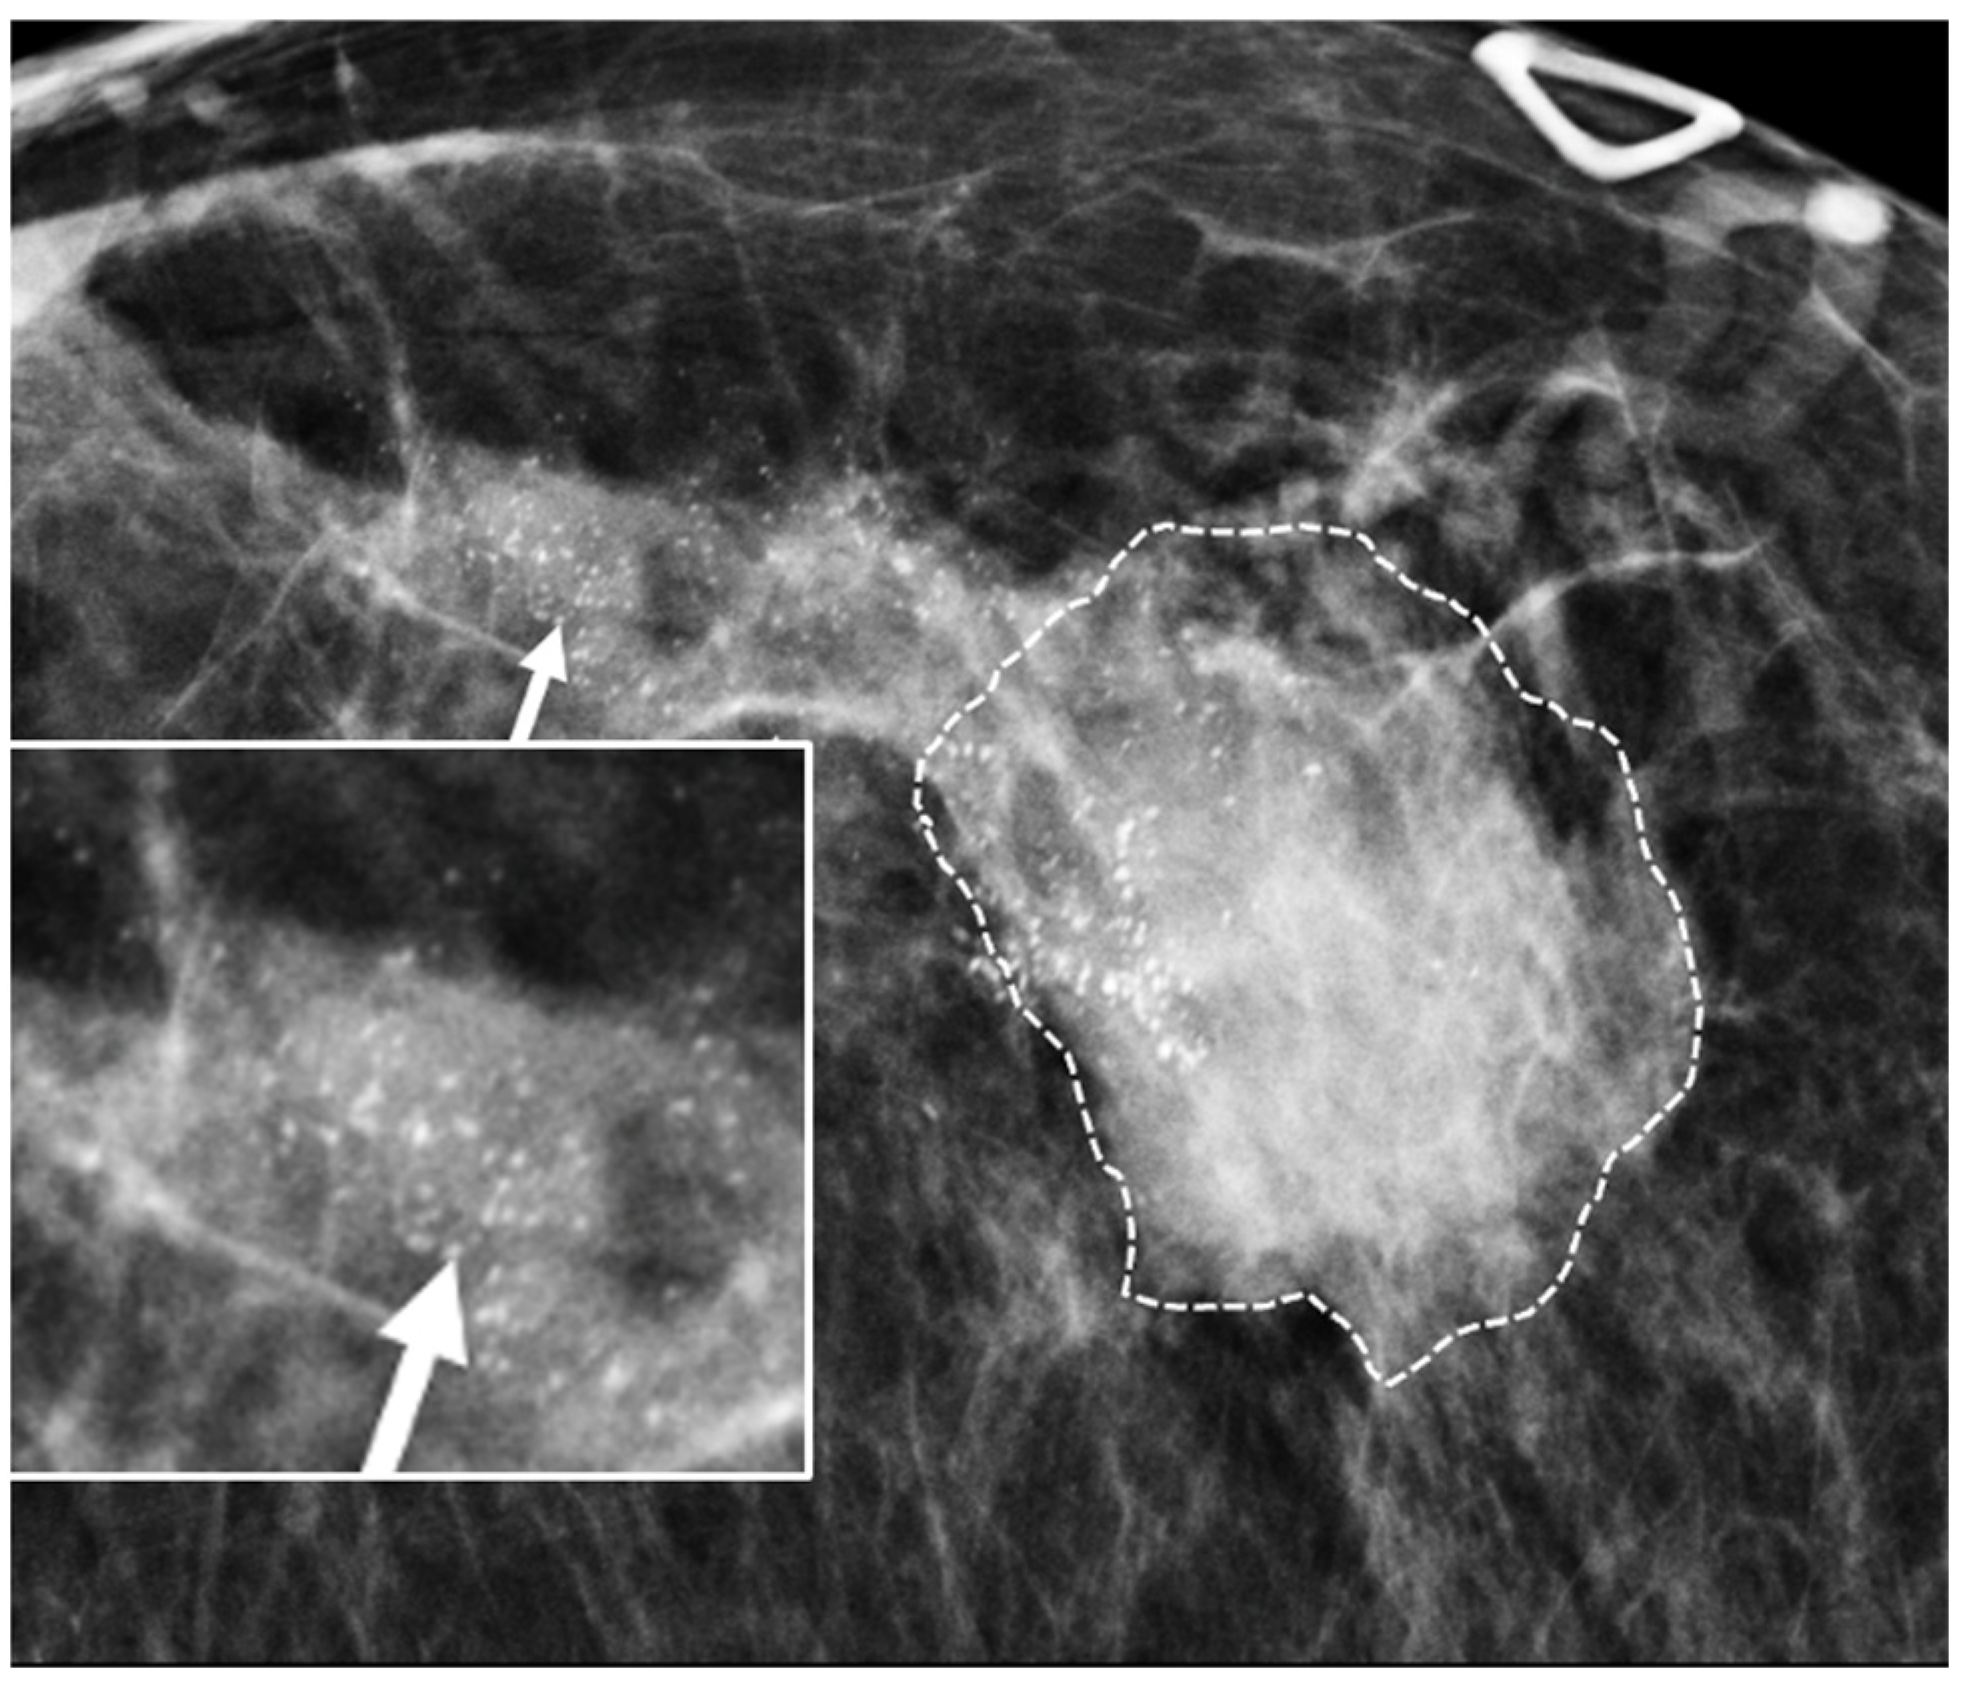

Digital Mammography. Breast cancer staging should include bilateral digital diagnostic mammograms (preferably 3D mammograms or tomosynthesis) to evaluate the extent of disease. Although cryoablation is generally performed under ultrasound or CT-scan guidance, high-quality mammography might reveal additional areas of cancer in the same region of the breast (multifocal cancer) or in a different region of the breast (multicentric cancer) that might impact patient selection or alter the cryoablation treatment plan. Multicentric and multifocal breast cancer is generally regarded as a contraindication to cryoablation. Pre-treatment assessment of the mammograms should seek the detection of spiculations (radial tumor extensions) and/or microcalcifications that might reach beyond the main tumor mass and require incorporation in the cryoablation treatment zone (Figure 1). Since mammography is the only imaging study that reliably shows microcalcifications, mammography plays a particularly important role in determining disease extent when suspicious microcalcifications are part of the disease process. Consequently, patients who are generally opposed to obtaining screening mammograms should be encouraged to have at least one set of pre-treatment diagnostic mammograms to exclude the presence of suspicious microcalcifications that could impact patient selection and/or treatment planning.

Figure 1.

Mammogram showing density corresponding to a palpable mass (see dashed lines) as well as suspicious microcalcifications (arrows) and inset image showing magnified view of white punctate calcifications extending beyond the palpable mass.

Contrast-Enhanced Breast MRI. Contrast enhanced breast MRI improves assessment of disease extent, including detection of spiculations, multifocal, multicentric, or contralateral disease, which might impact eligibility for cryoablation or alter the overall treatment plan (Figure 4). Contrast-enhanced breast MRI has the added value of permitting 3-D image reconstruction to permit viewing of the tumor from various angles for a more comprehensive assessment of tumor shape and size. Breast MRI for cancer evaluation requires the use of an intravenous contrast containing gadolinium that can be safely administered with minimal short-term and long-term risks. However, patients unwilling or unable to receive gadolinium might be able to access dedicated breast-only diffusion weighted MRI, which has limited availability in the U.S.

Figure 4.

Contrast-enhanced breast MRI image showing multifocal disease indicated by mass-like enhancement of dominant mass (indicated by single arrow and encircled with hash marks) as well as mass-like enhancement of a second focus of disease (indicated by double arrows and encircled with hash marks). The second focus was mammographically-occult.